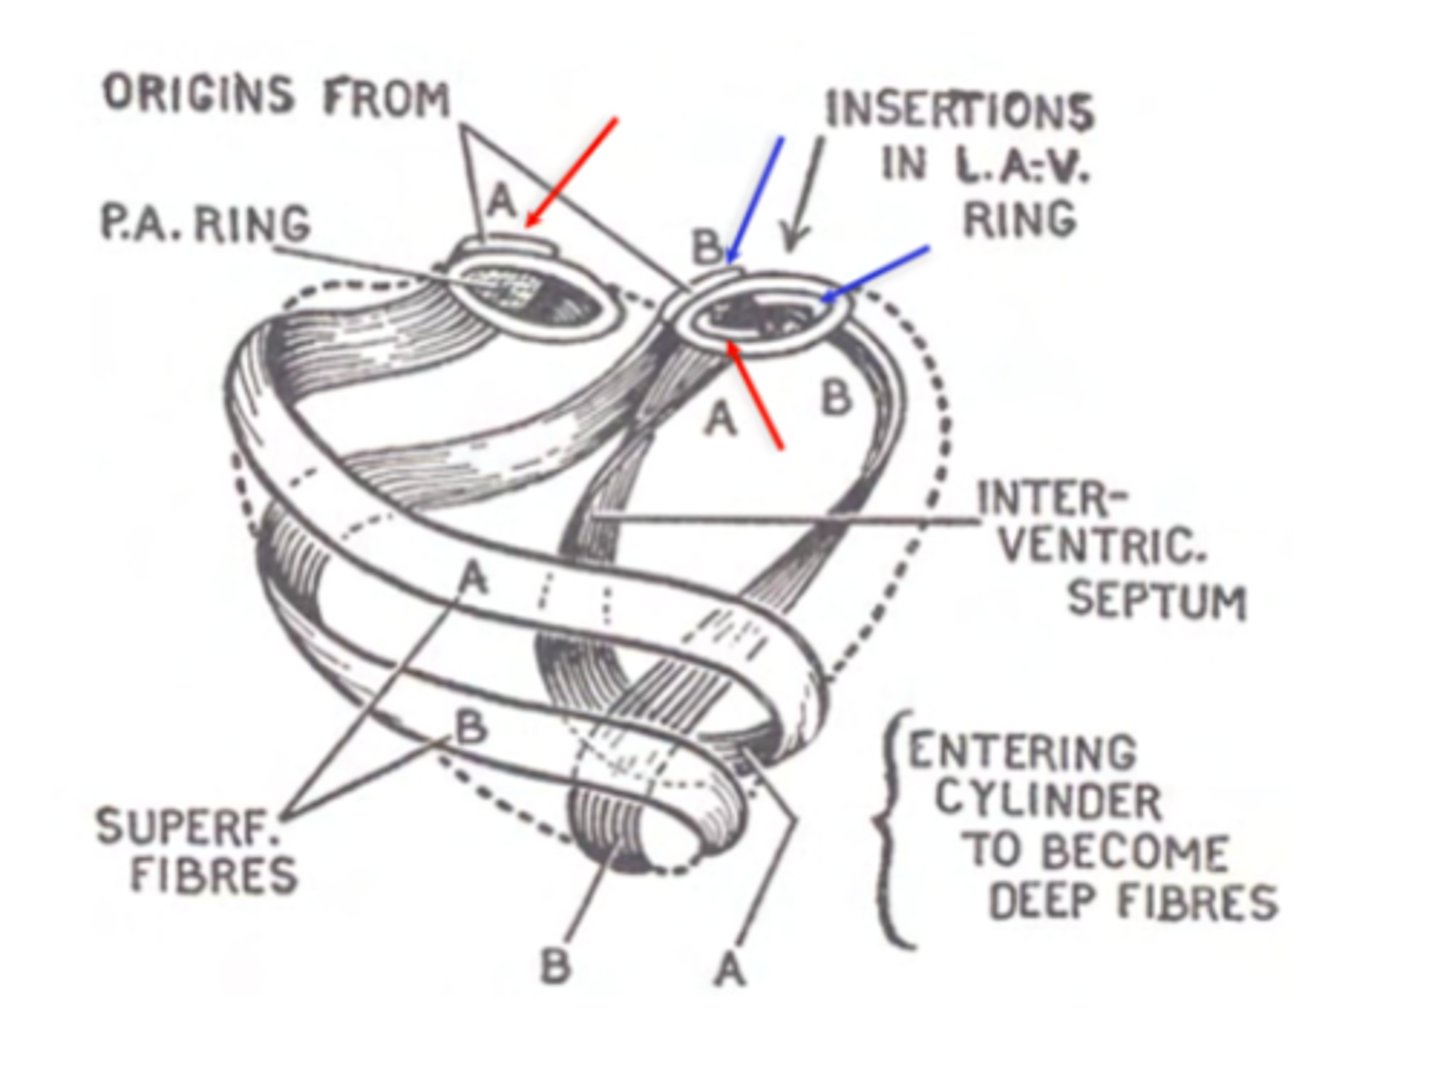

What are type A fibers in myocardium?

Start at one ring of the cardiac skeleton and finish at the other.

What are type B fibers in myocardium?

Begin at one ring and finish at the same ring where they started (either right or left).

Reinforce the ventricles

What are the layers of myocardium that divide the chambers of the heart?

left : superficial, middle and deep

REMEMBER LEFT IS THICKER DUE TO THE HIGH PRESSURE OF THE AORTA